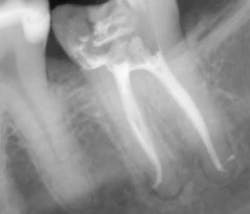

Canals are carefully dried with paper points. Insert the gutta-percha with AH sealer in the canal to working length, and take it back out. Add additional sealer to the gutta-percha, and then in a gentle pumping motion insert gutta-percha back to working length. Sear off access with a thermal pen and apply gentle pressure with a condenser.

Using a pumping motion and adding additional sealer ensures that voids within the canals get filled. This generates the “puff” effect with small amount of sealer being extruded from the apex of canals. It also helps ensure accessory canals are not left unfilled.